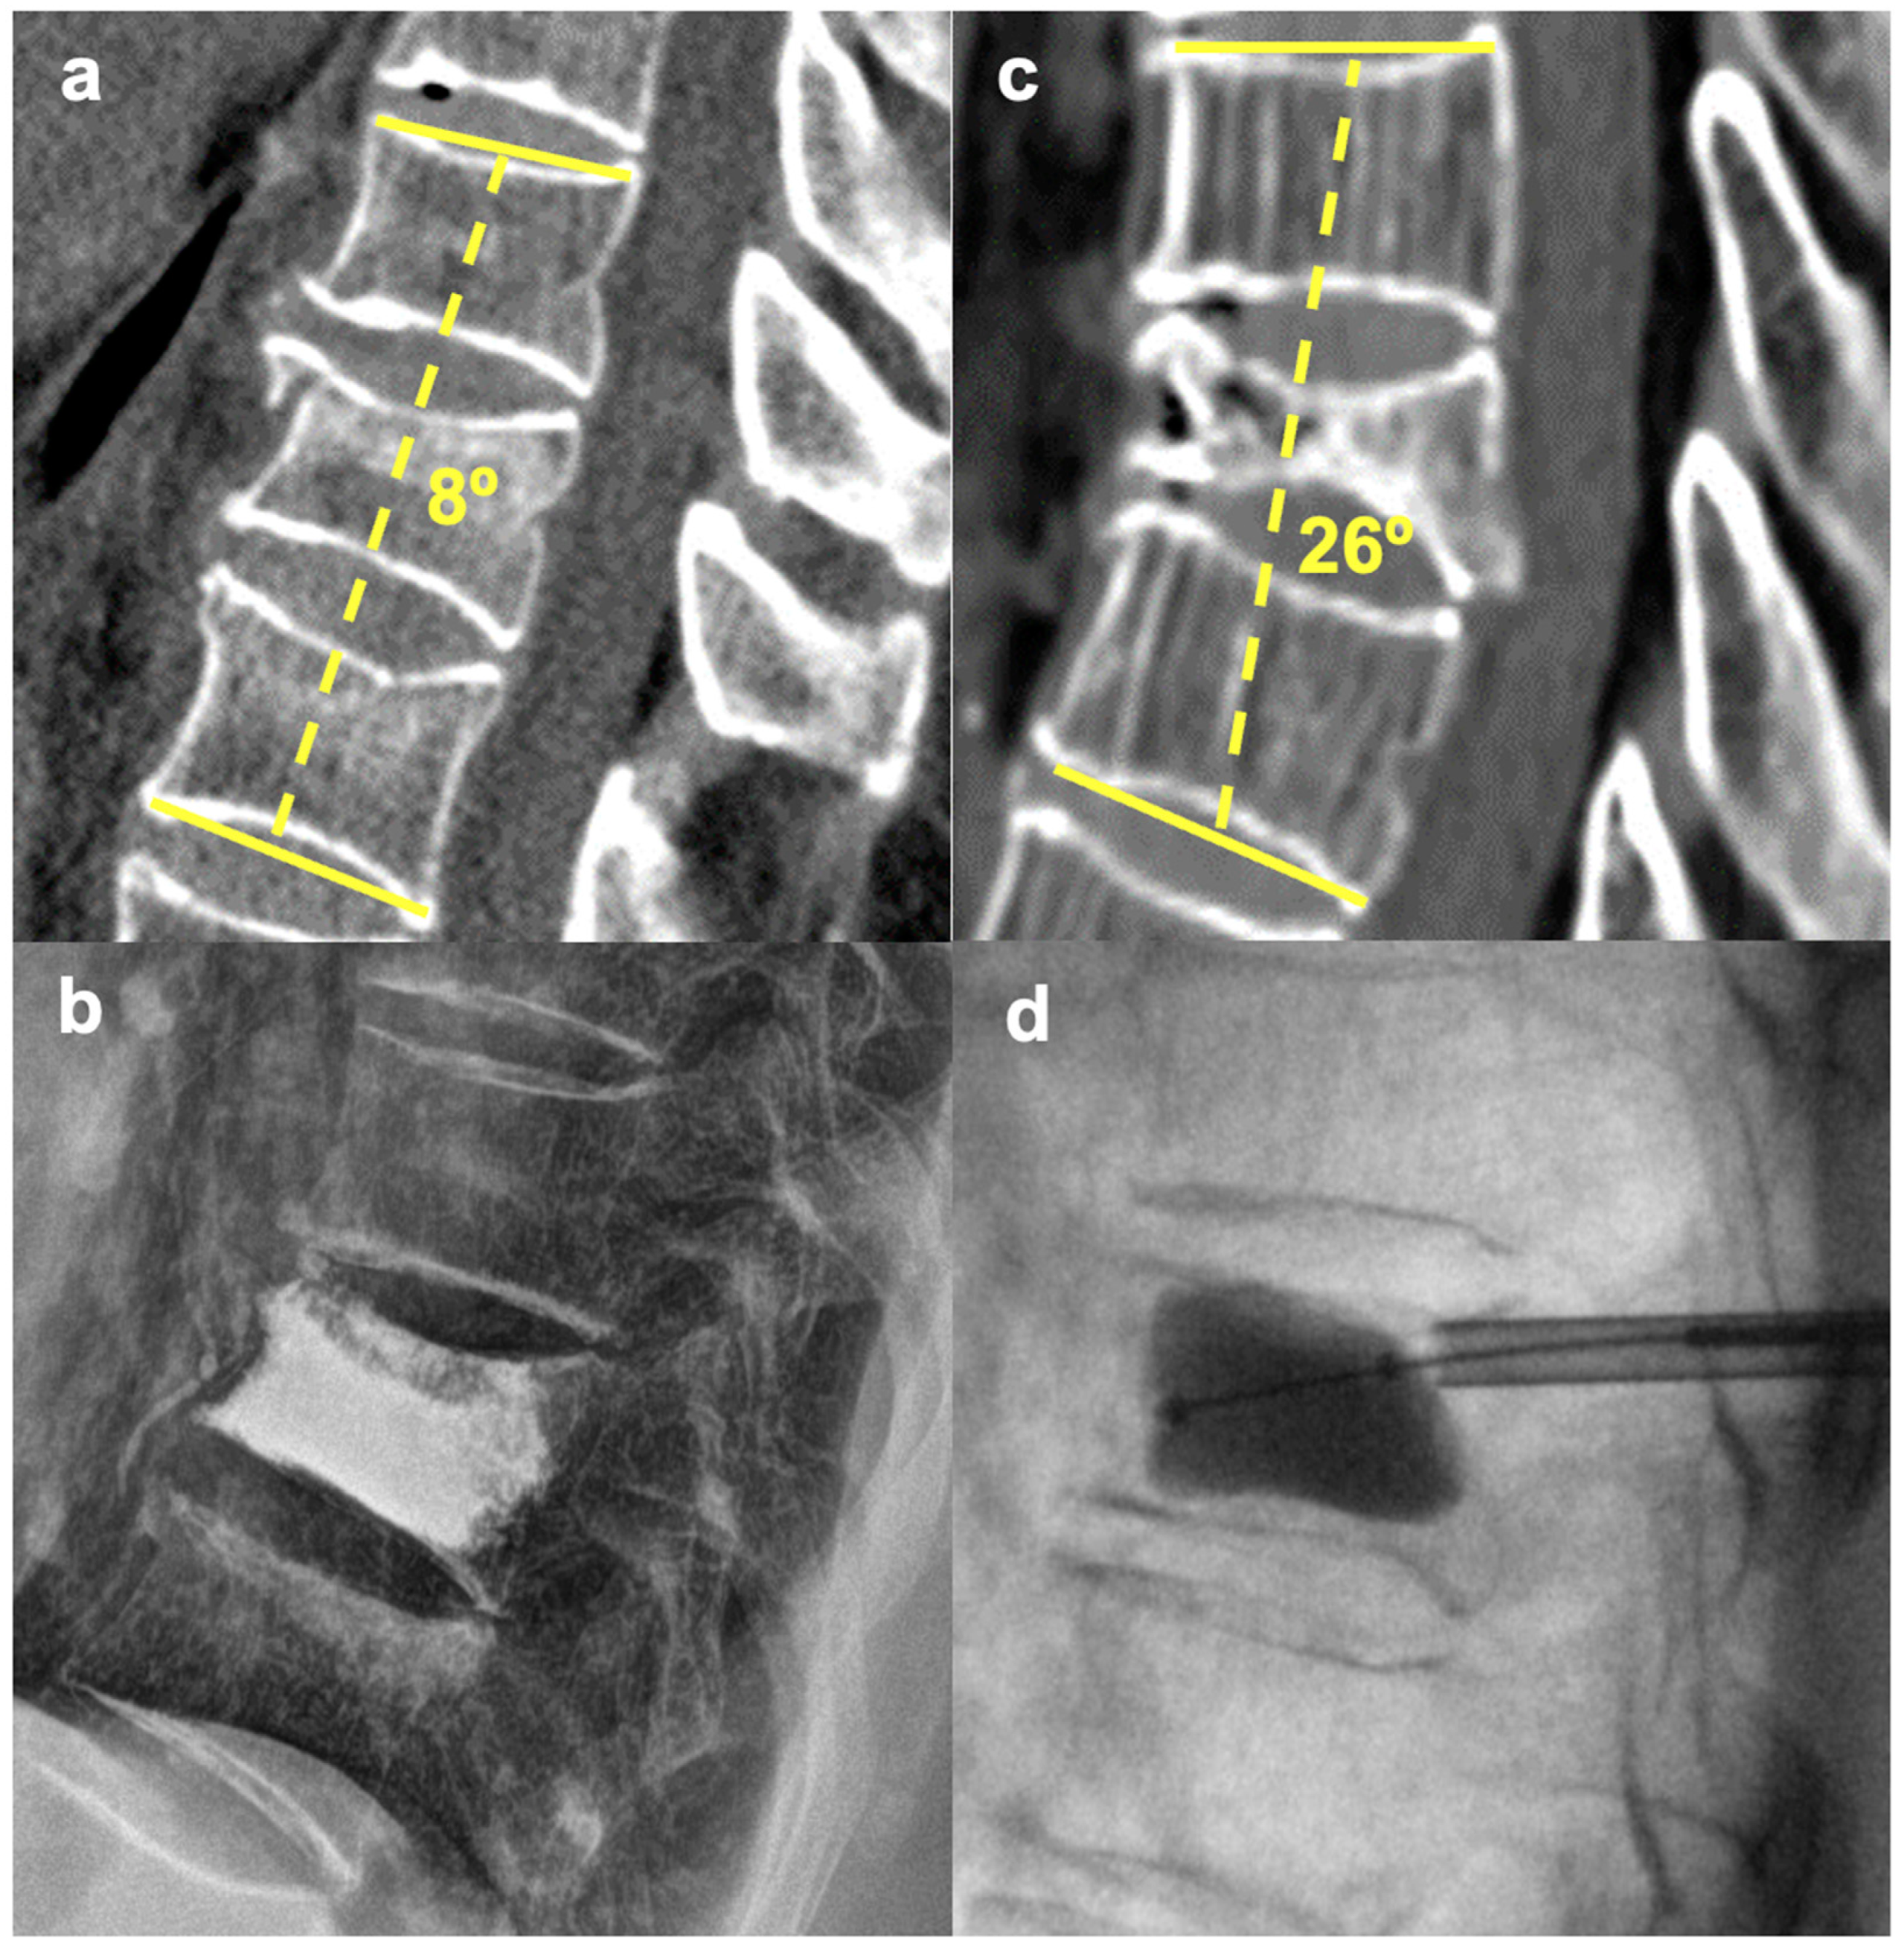

2.2. Surgical Technique